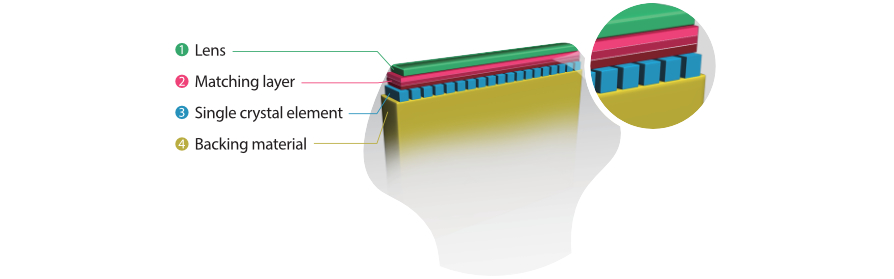

???? ??? 3T Transducer Technology?

M9? ???? ?? ???? ?? ??? ??? ?????? ?????? ???? 3T ????? ??? ??? ????. ??? ??? ??? M9? ?? ??? ?? ?? ?? ? ?? ?? ???? ?? ???? ??? ?????.